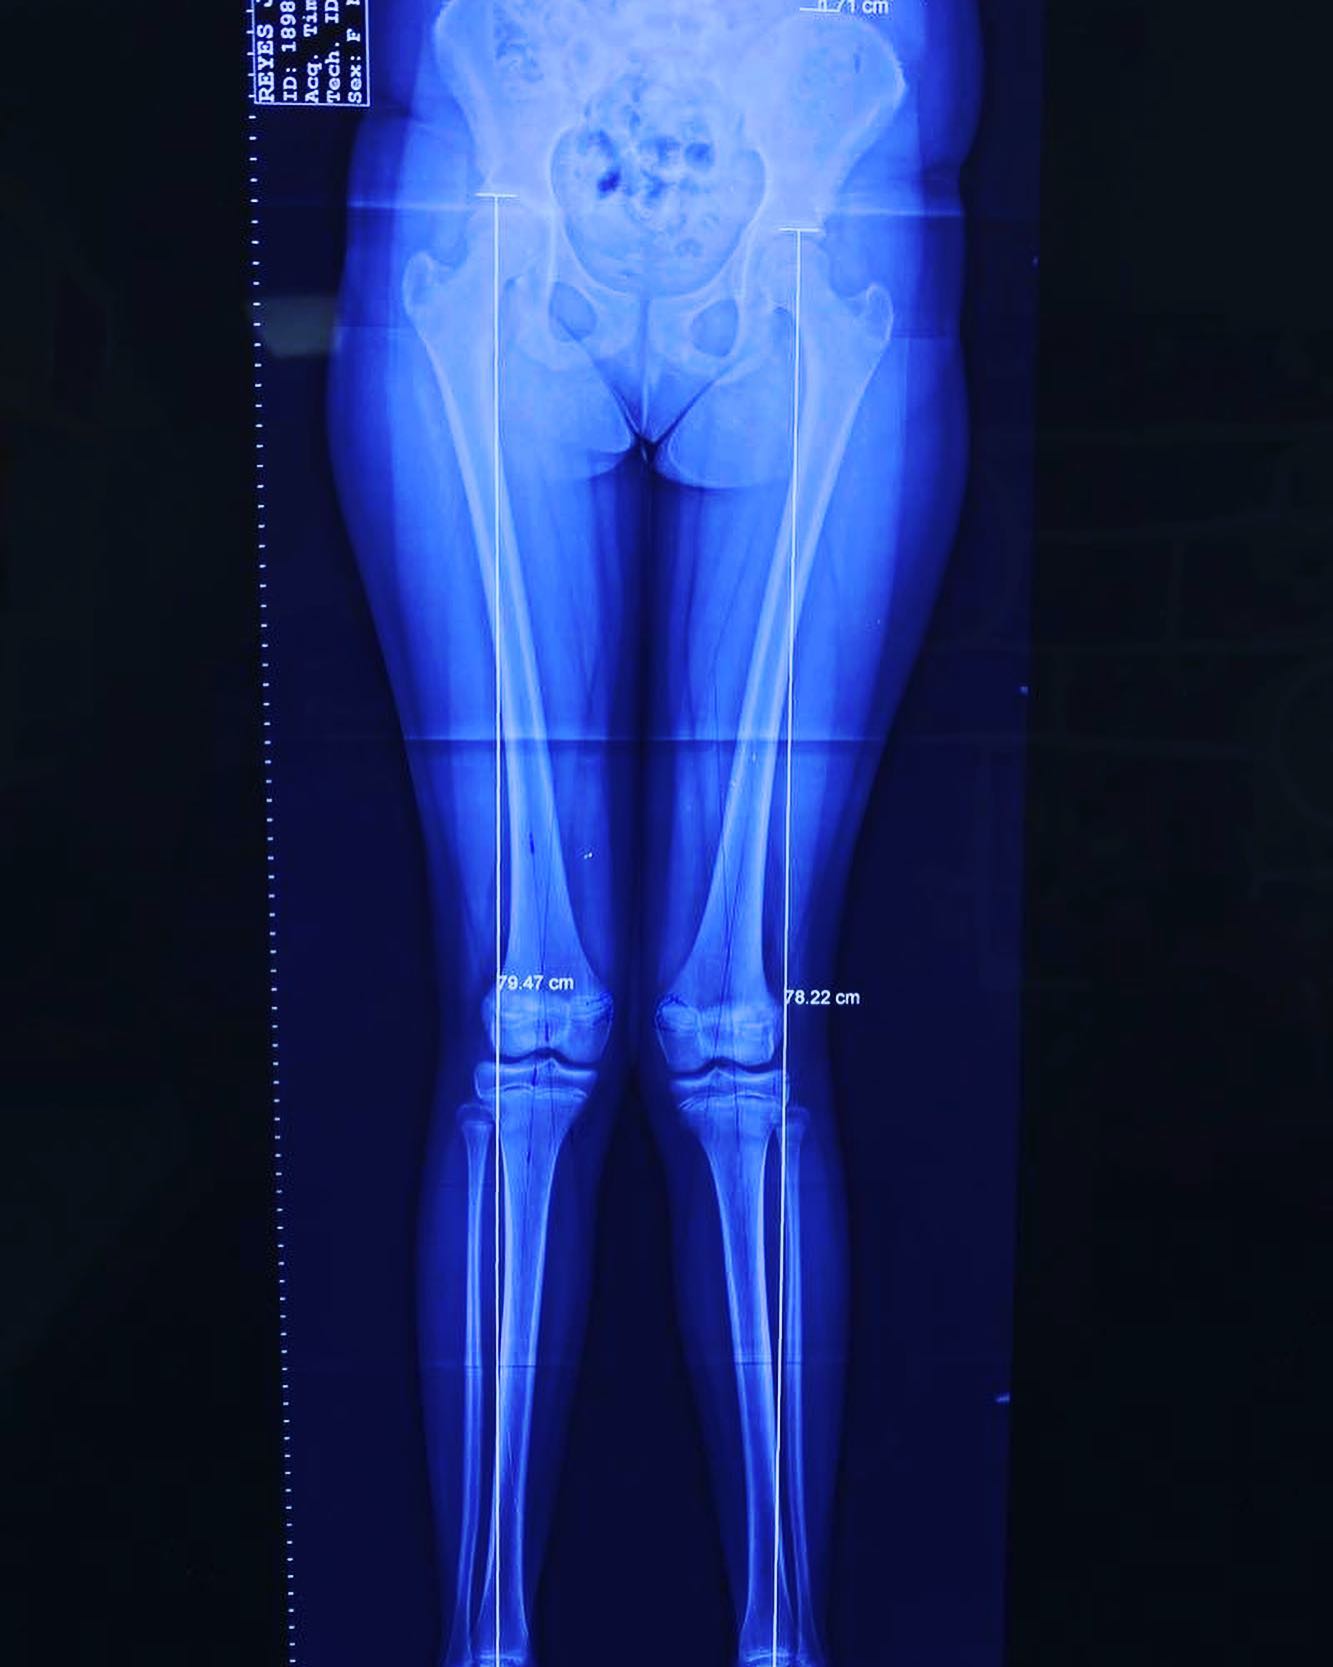

deformidad rodillas en valgo

Ella es mi pacientita Danna, de 13 años. Vino a consulta por una deformidad muy común: "Rodillas en Valgo”. Por suerte, llegó a tiempo y logramos corregirla al 💯. ¡Felicidades, Danna! Ahora sí, ¡a darle al gym! 💪